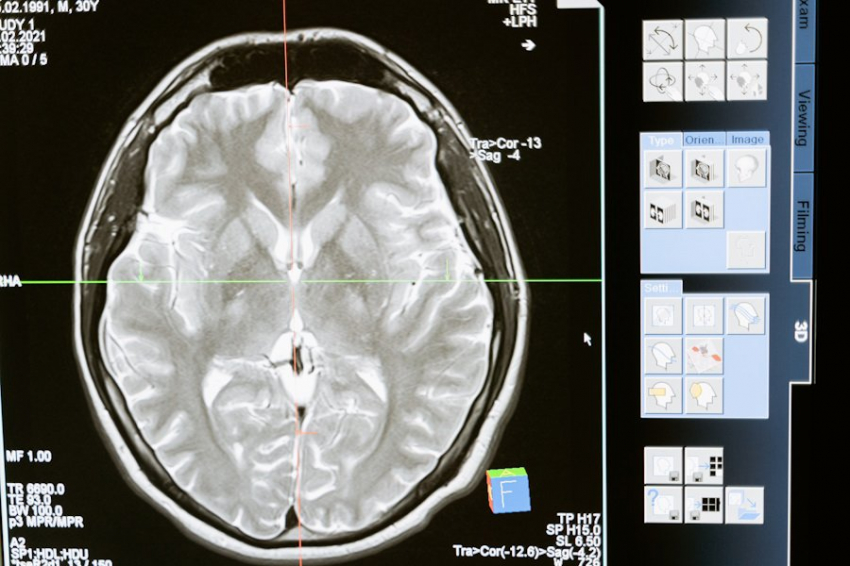

Быстрый сон начинается спустя 60-80 минут после засыпания и сопровождается активной работой мозга. Именно в это время у человека возникают сновидения, а также формируются способности к обучению и творчеству. Учёные исследовали, как нейроны в верхней части ствола мозга, области, называемой мостом, влияют на протекание этой фазы у лабораторных мышей.